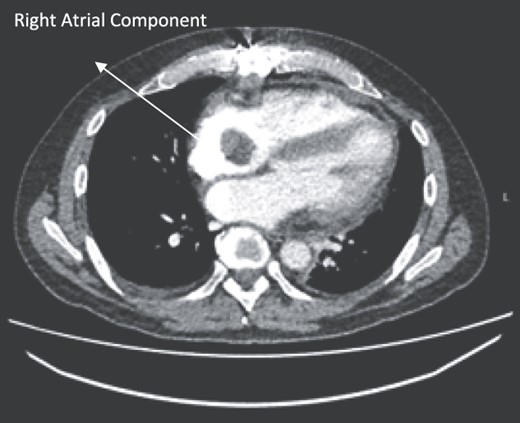

A 52-year-old gentleman was admitted to a district general hospital for shortness of breath causing type 1 respiratory failure with oxygen saturations of <90% despite high flow oxygen. His past medical history was unremarkable, and he was usually fit and well. A CT Pulmonary Angiogram (CTPA) was undertaken, which showed a heterogeneous oval-shaped lesion measuring 15 × 9 × 14 cm3 between the heart and the diaphragm, with a median attenuation of 35 HU and no enhancement during the arterial phase. Further solid lesions of 14 mm in the right lower lobe and 5 mm in the right upper lobe raised the suspicion of a primary cardiac sarcoma with pulmonary metastasis. This is shown in Fig. 1. Subsequent urgent CT staging (Fig. 2) was undertaken, which confirmed an indeterminate space occupying the inferior pericardial space, right atrial (RA) filling defect and anterior nodular pericardial thickening. No intra-abdominal or bone lesions were identified. An echocardiogram also confirmed these finding with the addition of no flow through the tricuspid valve (TV), as shown in Fig. 3.

CTPA showing oval-shaped heterogenous lesion as well as RA filling defect.